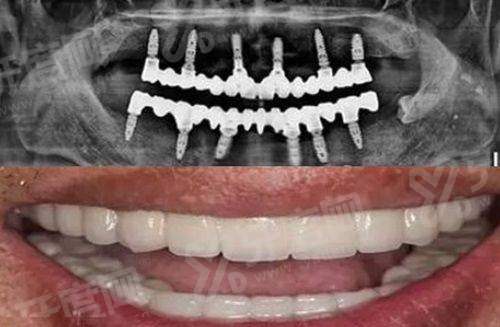

1、数字化种植技术:引进口腔CBCT设备,术前通过3D扫描精细获取牙槽骨数据,医生根据三维重建模型制定种植方案,实现“精细植入、微创微痛”,缩短手术时间,减少术后肿胀。

南平延平植雅口腔全口种植牙价格:3万元起